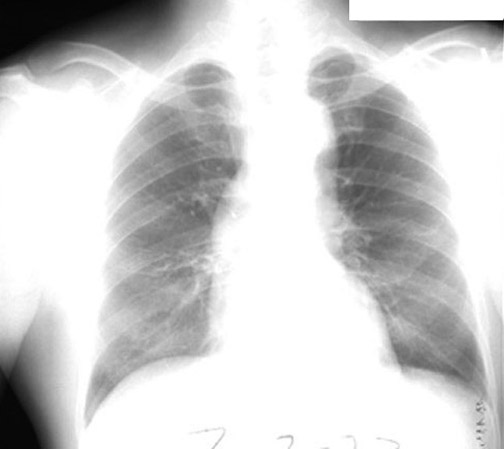

Lung Abscess - Aspiration

• Superior segment RLL dense pneumonia

Alcoholic presented with fever cough and weight loss of 2 weeks duration. Sub acute onset of pneumonia, typical of anaerobic lung abscess.

• Superior segment pneumonia